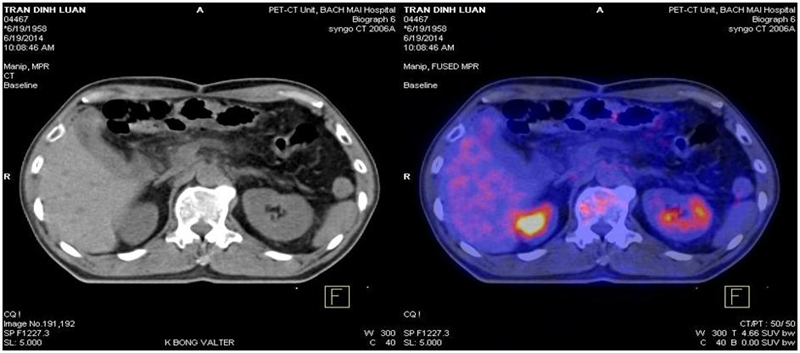

Bệnh nhân được chỉ định chụp PET/CT đánh giá sau điều trị: Kết quả không thấy hình ảnh tăng hấp thu và chuyển hóa F–18FDG bất thường trong cơ thể.

Hình 1: Hình ảnh chụp PET/CT toàn thân: Không thấy hình ảnh tăng hấp thu hay chuyển hóa bất thường F-18FDG trong cơ thể